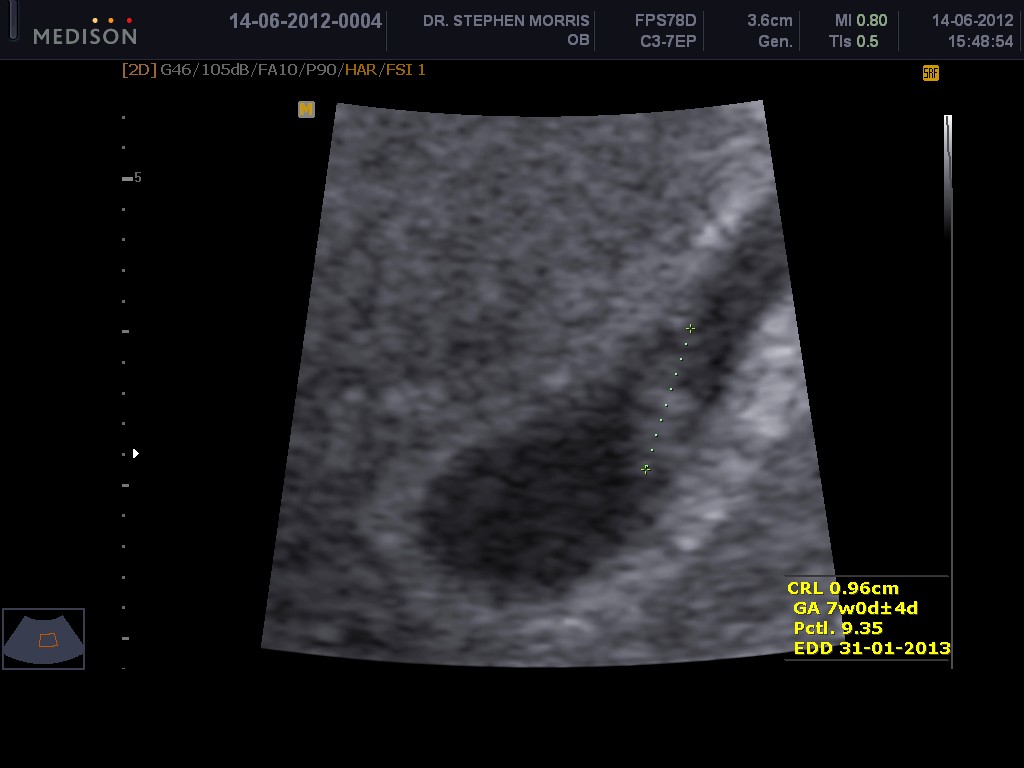

Dit was ook ons eerste scan hierdie week.  Die dokter het drie of vier spreekkamers en jy wag eers in die wagkamer, daarna in die spreekkamer, dan kom die midwife(!?) met jou praat om al die 'boring' goed te vra en in te vul en daarna kom die dokter om die scan te doen. Die dokter is heel kalm, asof hy 100 babas 'n dag 'deliver' ( 'vang' laat dit heeltemal te maklik klink as jy na al die brosjures kyk wat hy gegee het).

Dis nog so bietjie van 'n skok/opgewondenheid. Die realiteit het nogals ingeskop met die hoor van die hartkloppie. (Tweelinge is mos in die families. Net een hartklop. Hierdie keer.)

'n Paar fotos:

Hartklop duidelik sigbaar!

Volgens die dokter (en die scan) is ons 7 Weke swanger :-)

Expected Date of Arrival 31-01-2013